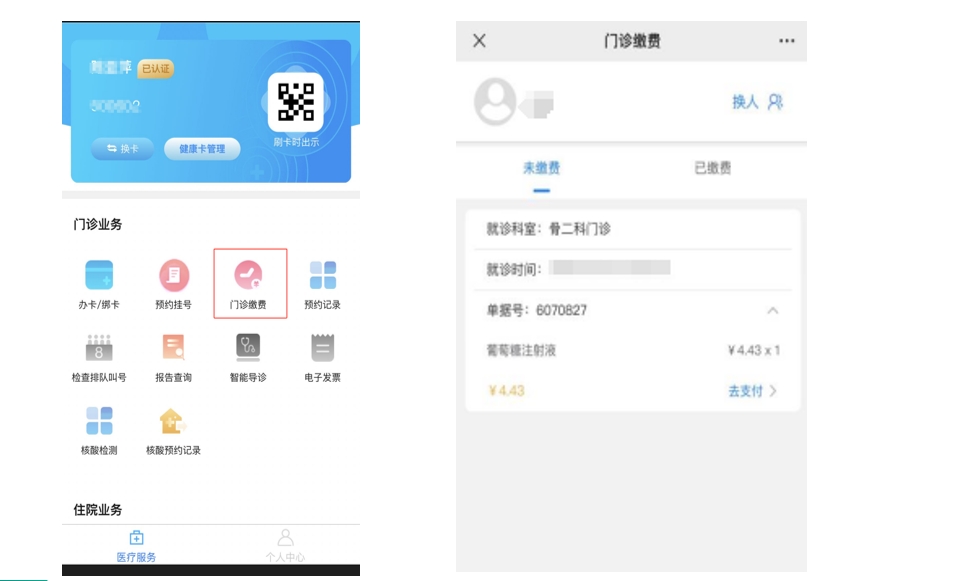

六、医院线上预约挂号系统源码,掌上医院源码,微信公众号、支付宝小程序

实体医院线上预约挂号系统源码,主要面向大中型的医院机构,适用于各级公立和民营医院用来搭建互联网医院平台,可对接院内his、lis、pacs系统。多家三甲医院应用案例。

一款服务于三甲医院的预约挂号系统,它集合了预约挂号、预约记录、在线支付、医保支付、医保信息、电子报告、住院金预交、住院每日清单查看等功能模块。

预约挂号管理系统具备后台管理端和用户使用端,用户使用端包括:微信公众号、支付宝小程序。